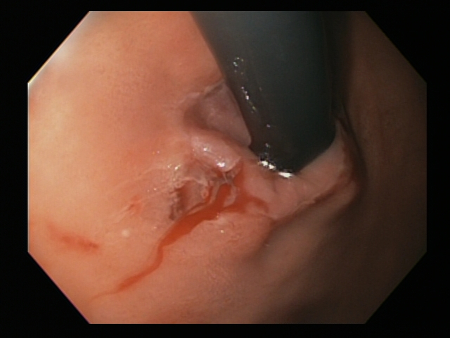

[Figure caption and citation for the preceding image starts]: A laceração de Mallory Weiss após aplicação de clipe do tipo "through-the-scope" resulta em hemostasiaDo acervo pessoal de Douglas Adler; usado com permissão [Citation ends].